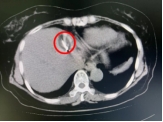

术中影像

病灶 毗邻心脏

介入科团队在CT影像监测与引导下,准确将消融探针插入肿瘤内,将肿瘤组织迅速冷却至-196℃,使癌细胞迅速降温,形成的“冰球”效应能够让医生直观监控,精细控制冷冻范围,确保完全覆盖肿瘤病灶并进行杀伤,冰冻后迅速复温至80℃,导致组织内肿瘤细胞脱水破裂,肿瘤细胞迅速死亡。